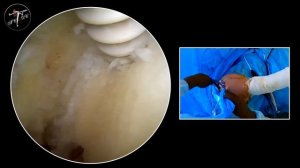

![Операция на плечевом суставе]() 4:46

4:46